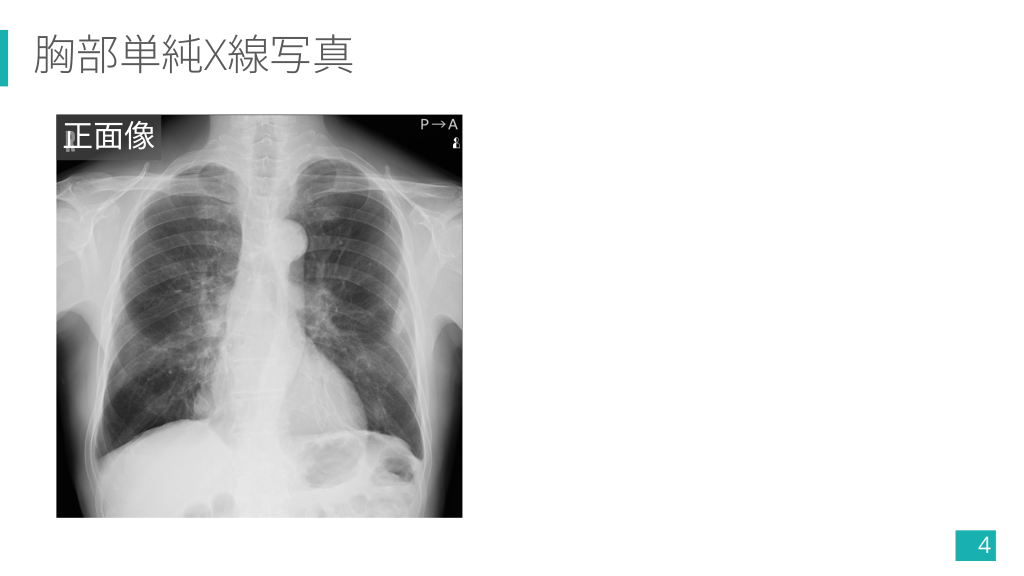

胸部単純X線写真 正面像 4

胸部単純X線写真 Ø 多発する不整軟部影や石灰化. Ø 右下肺野腫瘤影. Ø 左下肺野索状影. アスベスト関連疾患?? 13